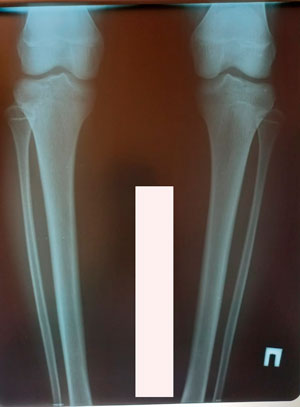

Исходник - 14 лет.

Дата операции - 16.12.2020